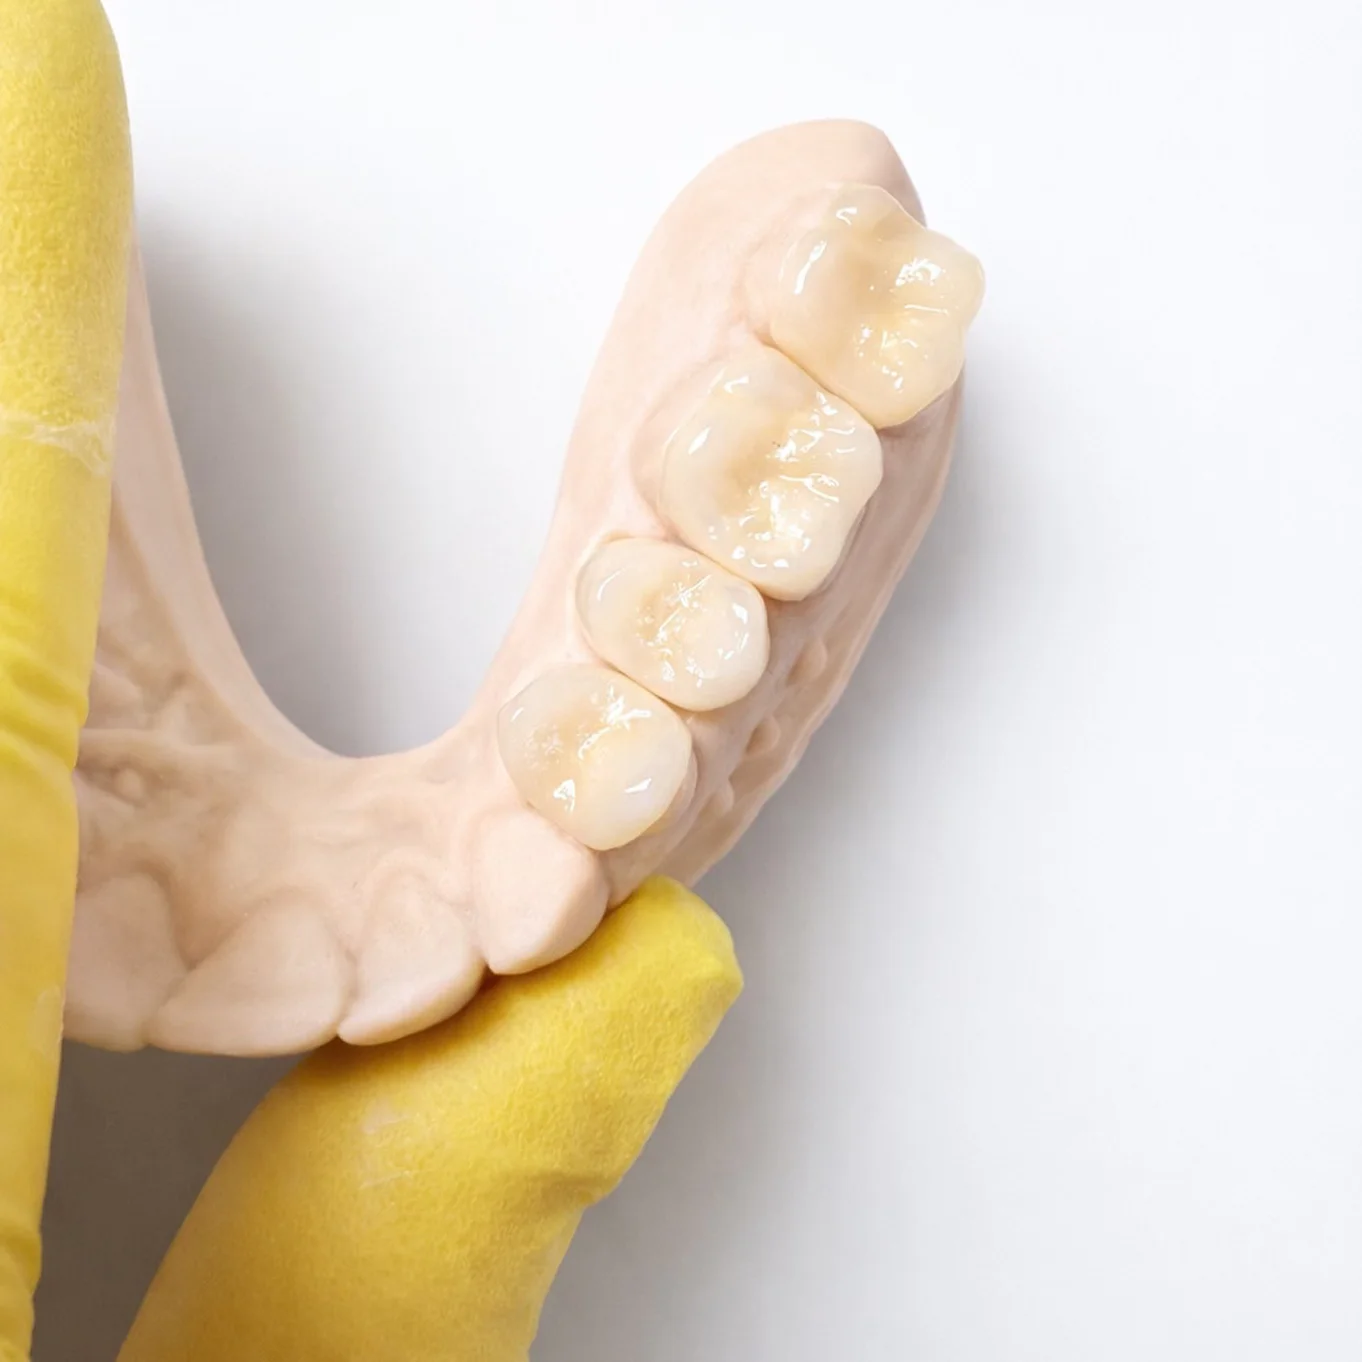

Керамічні вкладки служать 10–15 років і більше. Вони зберігають колір, не стираються, допомагають утримувати правильну висоту прикусу та відчуваються як рідний зуб.

Керамічна вкладка — використовується, коли зруйновано понад 50% зуба. Вона міцніша, довговічніша (10–15 років), точно відтворює анатомію та витримує високе жувальне навантаження.